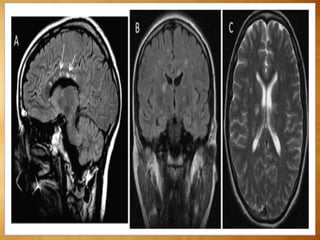

T1WI

 Hypo- or isointense - correlates with axonal

destruction.

Beveled or "lesion-within-a-lesion" appearance -

faint, poorly delineated peripheral rim of mild

hyperintensity (lipid peroxidation and macrophage

infiltration ) surrounds sharply delineated

hypointense black holes.

The corpus callosum becomes progressively thinner

and is best delineated on sagittal T1WI.

Lesion within a lesion apperence

T2WI

Multiplehyperintenselinear,round,orovoidlesions

surroundingthemedullaryveinsthatradiatecentripetally

awayfromthelateralventricles

Triangularshapewiththebaseadjacenttotheventricleon

sagittalFLAIRorT2WIimages.

T1WI  Hypo- orisointense - correlates with axonal destruction. Beveled or "lesion-within-a-lesion" appearance - faint, poorly delineated peripheral rim of mild hyperintensity (lipid peroxidation and macrophage infiltration ) surrounds sharply delineated hypointense black holes. The corpus callosum becomes progressively thinner and is best delineated on sagittal T1WI.

Lesion within alesion apperence